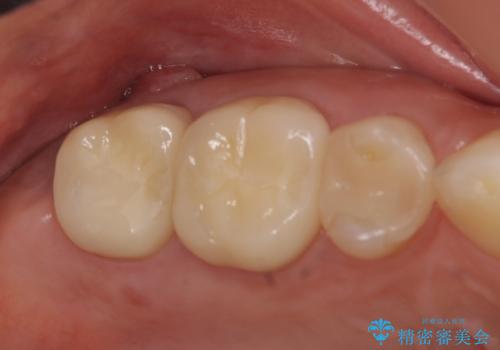

- 右下5番目の歯がしみるといらっしゃった方の症例です。

銀歯及び虫歯を除去し、適合に優れたPGA(ゴールド)インレーにて修復を行いました。